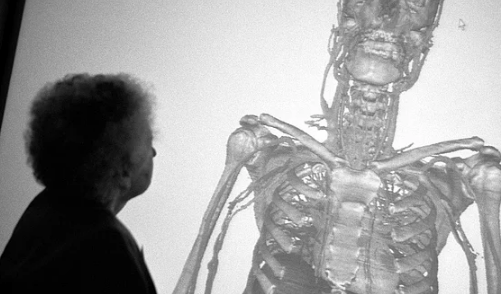

2000 yılında doktorlar Sue'ya sadece 1 yıllık ömür biçmişlerdi. Fakat vücudunu bağışlayan kadın 15 yıl daha yaşadı ve bu süreç içinde sık sık hastaneyi ziyaret etti.

Sue bu ziyaretlerinde hem tıp öğrencileri ile tanışıyor hem de öldükten sonra vücudunun nasıl kesip fotoğraflanacağı hakkında daha detaylı bilgi alıyordu.